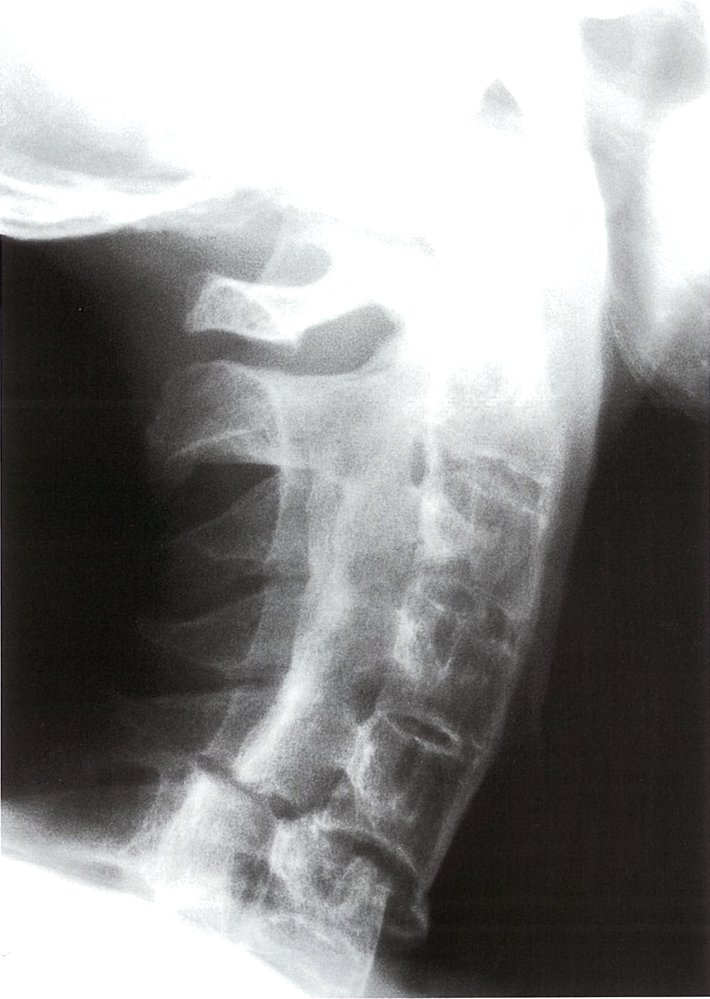

Spine (AP and lateral views)

• Indications

• Pain in the cervical, thoracic, or lumbar spine

• Suspicion of AS remains after a negative radiograph and MRI of sacroiliac joints

• Characteristic findings

• Loss of lumbar lordosis: abnormal straightening of the spine

• Ankylosis of costosternal and costovertebral joints

• Dagger sign

• A radiodense line running through the center of vertebral bodies on AP view

• Caused by ossification of vertebral ligaments

• Bamboo spine: seen in later stages and is caused by the following

• Ossification of outer fibers of the annulus fibrosus resulting in ankylosis (fusion) of intervertebral joints

• Syndesmophytesbetween adjacent vertebral bodies (see “Syndesmophytes vs. osteophytes”)

• Shiny corners sign: reactive sclerosis of the superior and inferior margins of vertebrae

Early stages of AS may be unidentifiable on x-ray (low sensitivity for early-stage). Hence, a patient with several classical clinical and laboratory findings fulfills the diagnostic criteria for AS even if x-ray findings are inconclusive. [5][15]